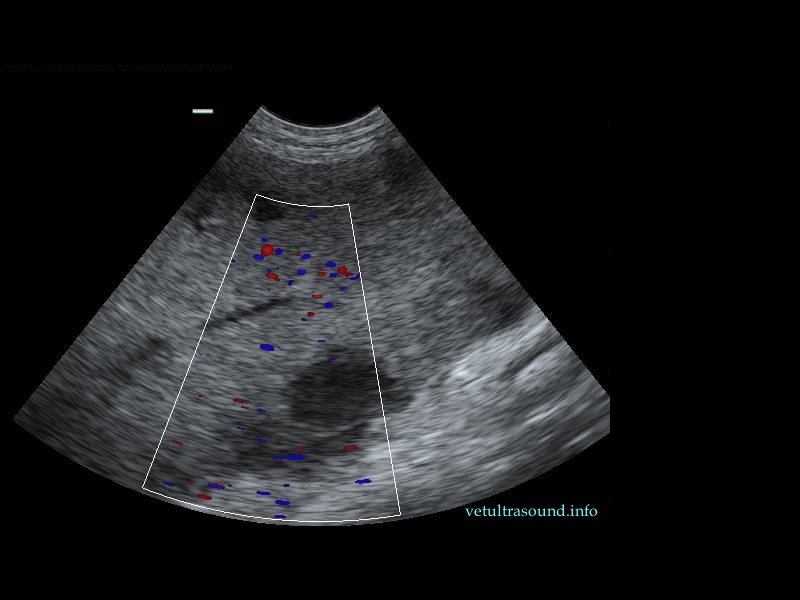

Ευρήματα: Η κεφαλή του σπλήνα βρέθηκε μετατοπισμένη ( στραμένη προς τα οπίσθια άκρα) με υποκαψικές περιοχές υποηχογένειας, χωρίς αιμάτωση (pic 1,2,3). Το τμήμα αυτό του σπλήνα ήταν διογκωμένο σε σχέση με το υπόλοιπο όργανο και το μεσεντέριο λίπος που το περιέβαλε ήταν έντονα υπερηχογενές. Στο συγκεκριμένο σημείο του σπλήνα τα μεγάλα αγγεία δεν είχαν ροή αίματος κατά τον έλεγχο με έγχρωμο Doppler (pic3). Αντίθετα το σώμα και η ουρά του οργάνου είχαν φυσιολογική αιμάτωση και μέγεθος (pic 4,5).

Διάγνωση: Η εικόνα αυτή θα μπορούσε να οφείλεται σε εμφράκτα τα οποία δημιουργήθηκαν είτε από θρόμβους ή σηπτικά έμβολα, είτε από μείωση της αιματικής ροής της περιοχής. Εξαιτίας της αλλαγής της θέσης του σπλήνα, του υπερηχογενούς μεσεντέριου λίπους που περιέβαλε την κεφαλή του οργάνου και των εμφράκτων στο παρέγχυμά του, η διάγνωση που τέθηκε είναι η μερική συστροφή του σπλήνα ή η παροδική διακοπή της αιμάτωσής του. Αυτό θα μπορούσε να έχει προέλθει από διάταση ή μερική στροφή του στομάχου, λαμβάνοντας υπόψιν το ιστορικό και τη φυλή του σκύλου. Η αιματουρία προήλθε πιθανά λόγω αιμόλυσης, εξαιτίας της συμφόρησης του σπλήνα. Έγινε σπληνεκτομή όπου και επιβεβαιώθηκε η μερική στροφή του οργάνου με αποτέλεσμα τον στραγγαλισμό μεγάλου μέρους των αγγείων του.